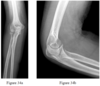

- Figures 34a and 34b are the radiographs of a 22-year-old woman who sustained an elbow injury after a fall. In the emergency department, her skin is noted to be intact. There is no tenderness over the medial elbow or the distal radioulnar joint. What is the best treatment option?

- Radial head arthroplasty

- Long-arm cast for 3 weeks

- Excision of the fracture fragments

- Open reduction and internal fixation (ORIF)

- Early motion with a functional brace

- Open reduction and internal fixation (ORIF)

RECOMMENDED READINGS

Pike JM, Grewal R, Athwal GS, Faber KJ, King GJ. Open reduction and internal fixation of radial head fractures: do outcomes differ between simple and complex injuries? Clin Orthop Relat Res. 2014 Jul;472(7):2120-7. doi: 10.1007/s11999-014-3519-8. PubMed PMID: 24585322; PubMed Central PMCID: PMC4048425.

Yoon A, King GJ, Grewal R. Is ORIF superior to nonoperative treatment in isolated displaced partial articular fractures of the radial head? Clin Orthop Relat Res. 2014 Jul;472(7):2105-12. doi: 10.1007/ s11999-014-3541-x. PubMed PMID: 24577616; PubMed Central PMCID: PMC4048435.